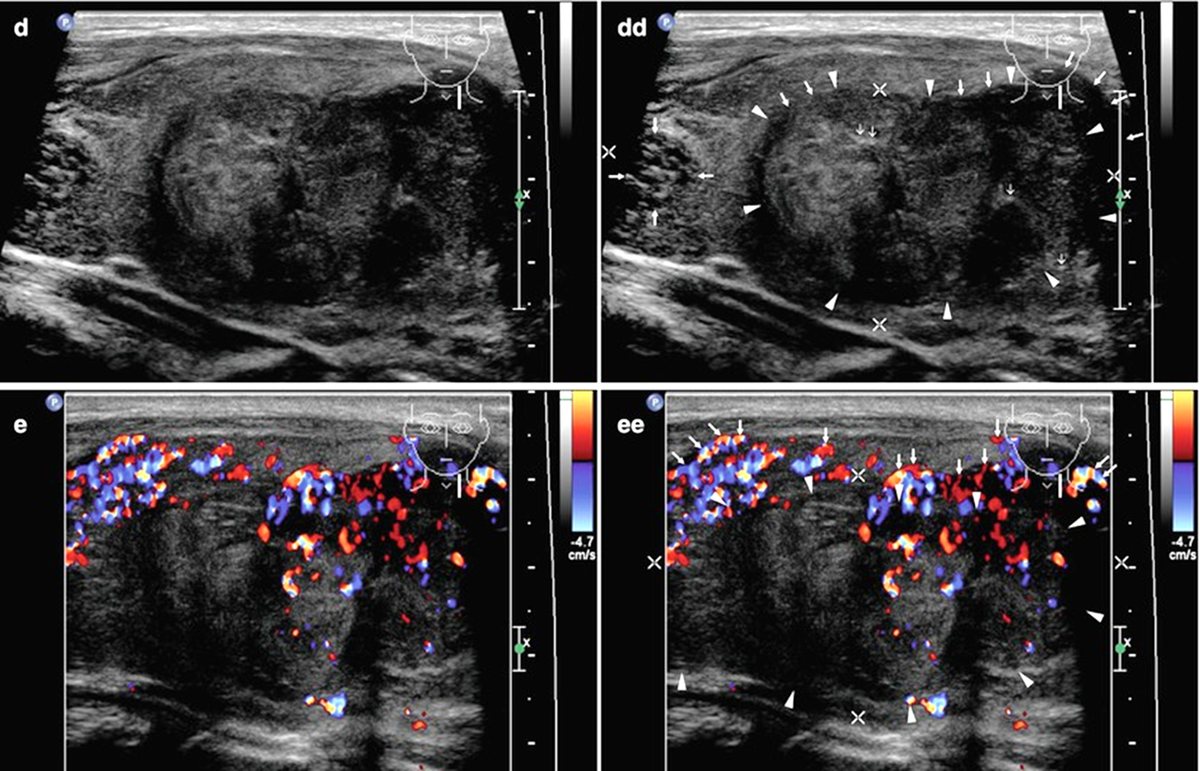

Анапластический рак щитовидной железы при УЗИ

• Обычно визуализируется крупное диффузно-неоднородное бесформенное гипоэхогенное образование, занимающее всю долю, без четких границ.

• В 78% случаев наблюдаются зоны некроза опухоли, в 58% случаев - кальцинаты.

• В 47% случаев опухолевые узлы АР ЩЖ окружены зонами узловой гиперплазии.

• Как правило, опухоли хорошо васкуляризированы за исключением зон некроза.

• Отмечается, что в момент исследования опухоль обычно находится в уже далеко зашедшей клинической стадии и распространяется практически на всю ткань железы.

• Экстракапсулярное распространение с инфильтрацией трахеи, пищевода, мягких тканей шеи наблюдается в 30% случаев; может быть тромбоз внутренней яремной вены и опухолевая окклюзия общей сонной артерии.

• В 80% случаев наблюдаются метастазы в регионарные лимфоузлы в виде увеличенных гипоэхогенных образований округлой или овальной формы на стороне локализации новообразования, реже на противоположной.